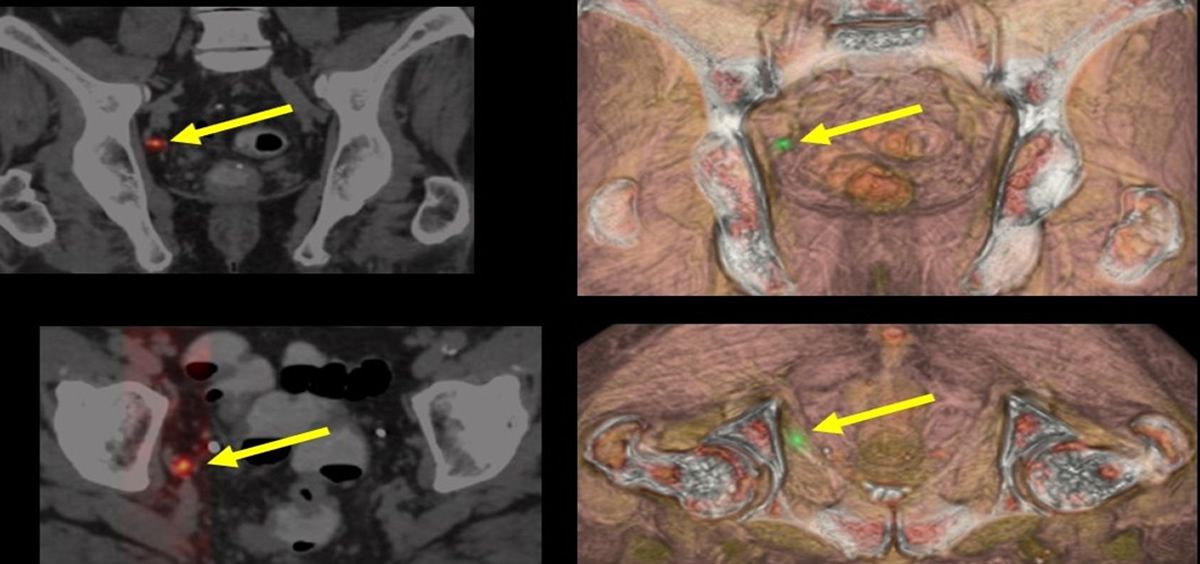

La imagen anatómica CT y funcional de la gammagrafía ósea en el cáncer de próstata ha sido claramente superadas por las dos exploraciones de imagen molecular avanzada como son el PET-CT (fundamentalmente con PSMA) y la RM multiparamétrica. El doctor Antonio Maldonado, Jefe de Medicina Nuclear e Imagen Molecular del Hospital Universitario La Luz de Madrid, ha asegurado que "la información aportada por ambas pruebas convierte a la PET-RM en pieza indispensable en todo lo que se refiere al manejo de estos pacientes”.

“La introducción de la imagen PET-CT PSMA a este dúo diagnóstico, permite aún más, mejorar en la correcta selección de las áreas con tumor dentro de la glándula prostática”, asevera Maldonado.

De acuerdo al doctor Antonio Maldonado, el PET-CT PSMA completa el escenario al ser la técnica que mejor permite detectar metástasis a distancia. “Desde el punto de vista oncológico, la valiosa información TNM molecularno está orientada tanto al tipo de tratamiento a aplicar sino a ser una fuente importante de información de pronóstico y supervivencia de la enfermedad”, resalta el experto.

Es, en concreto, la detección de enfermedad tumoral ante recidiva bioquímica donde la imagen molecular avanzada PET-CT con radiofármacos PSMA (18F o 68Galio) supera al resto de pruebas de imagen. “Su información es clave para la toma precoz de decisiones de tratamiento, mejorando de esta forma espectacularmente el control de la enfermedad”, matiza el doctor Maldonado.

Por último, el doctor Antonio Maldonado afirma que la imagen molecular con PSMA permite la selección de pacientes y valoración de respuesta al tratamiento en casos de resistencias a las terapias convencionales como es el uso de 177Lutecio PSMA, clave en el arsenal de nuevas terapias radiometabólicas disponible en fases avanzadas de la enfermedad.